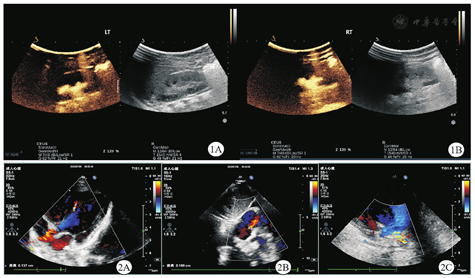

女,1岁,系G2P2,足月顺产,2022年8月2日就诊于河南省儿童医院郑州儿童医院神经遗传代谢病科。出生体质量为3.35 kg,无窒息抢救史。患儿自3月龄至今患泌尿道感染4次、肺炎1次;4月余认生,现会发"ma ma"音;大运动发育稍落后,7个月会独坐,10个月会爬,现可扶站。出生4个月时血常规检查结果提示白细胞17.95 × 109/L(正常参考值为5.10 ~ 14.10 × 109/L),红细胞3.98 × 1012/L(正常参考值为4.00 ~ 5.50×1012/L),血红蛋白115 g/L(正常参考值为107 ~ 141 g/L),中性粒细胞占比68.2%(正常参考值为13.0% ~ 55.0%),淋巴细胞占比25.4%(正常参考值为33.0% ~ 77.0%),中性粒细胞12.23 × 109/L(正常参考值为0.80 ~ 5.80 × 109/L),淋巴细胞4.56 × 109/L(正常参考值为2.40 ~ 8.70 × 109/L),C-反应蛋白31.52 mg/L(正常参考值为0 ~ 10.00 mg/L)。尿常规检查结果提示红细胞25/高倍视野[正常参考值为(0 ~ 3)/高倍视野],白细胞146/高倍视野[正常参考值为(0 ~ 5)/高倍视野],诊断为泌尿道感染。膀胱输尿管造影检查提示双侧膀胱输尿管反流(图1),肾盂积水(分离10.8 mm,轻度)。心脏彩色多普勒超声检查提示心脏肌部室间隔缺损(图2A)、卵圆孔未闭(图2B)、左肺动脉中远端稍窄(图2C)。出生6个月头颅及腰骶部MRI检查提示白质髓鞘化落后,双侧侧脑室增宽(图3),左肾略大,肾盂周围异常信号,尾椎上翘,余腰骶椎MRI平扫未见明显异常。患儿父母表型未见异常,否认近亲结婚及家族遗传病史。患儿有1个6岁的哥哥,现体健。患儿入院时体质量为8 kg、身高为72 cm,头围44.5 cm,生长发育落后于同龄儿。精神可,有额头突出、眼窝凹陷、宽眼距、眼裂下斜、耳后旋、薄上唇、腰骶部隐窝等外观特征。肺、腹检查未见异常,四肢肌张力低下,双侧膝反射可引出。抽取患儿及其父母的外周血样,进行全外显子组测序分析,结果提示患儿染色体17p13.3区存在1.49 Mb微缺失:seq[GRCH37]del(17)(p.13.3p.13.3)chr7:g.882 518-2 371 192 del(图4),父母该区域均未发现相同的缺失。本研究通过了河南省儿童医院郑州儿童医院伦理委员会的审查(2022-K-070),患儿父母均签署了知情同意书。